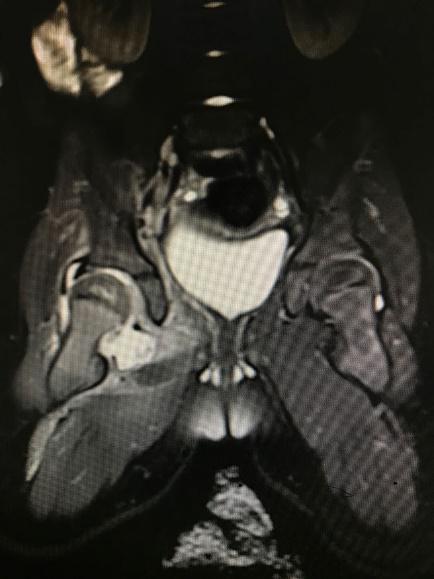

1 资料与方法 1.1 一般资料本研究为回顾性研究,获得医院医学伦理委员会审批(审编号:2020-IRB-035),通过检索本院的电子病例系统,搜索2016年1月1日至2018年12月31日期间出院诊断为“化脓性髋关节炎”的所有病例信息。纳入标准:(1)患儿临床症状、体征、影像学检查、关节液液培养、关节腔液白细胞计数(计数≥50 000 / mm3)、手术或病理证实的化脓性髋关节炎,见图 1~4;(2)关节腔穿刺或手术可见脓性标本。排除标准:(1)年龄>3岁;(2)穿刺或手术未能取得足够标本送检细菌培养者。

| 图 2 MR超示关节腔内积液 |